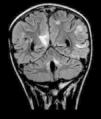

Niña de 9 años diagnosticada de meduloblastoma con resección subtotal y radioterapia. Se inicia quimioterapia con CCNU, vincristina y cisplatino. A las 2 semanas del primer ciclo ingresa por dolor abdominal, vómitos, astenia e insomnio. Presenta 2 crisis parciales complejas y en este contexto se detecta hipertensión arterial. Neurológicamente, está somnolienta y tiene una hemianopsia homónima izquierda. Se realiza una RM craneal donde se objetivan lesiones hiperintensas en secuencias T2 y FLAIR de localización subcortical parieto-occipital, imágenes compatibles con una leucoencefalopatía posterior reversible (fig. 1). Se inicia tratamiento con levetiracetam e hidralazina. Aunque tanto el cisplatino como la vincristina1 pueden desencadenar esta complicación neurológica, se retira inicialmente el cisplatino del protocolo quimioterápico, desapareciendo a las 72 h la hemianopsia, mejorando el nivel de consciencia y normalizando la presión arterial. Transcurridas 4 semanas. se repite la RM, donde se constata la completa resolución de las lesiones (fig. 2).

La leucoencefalopatía posterior reversible es una patología infrecuente en edad pediátrica. La RM es indispensable para el diagnóstico, caracterizada por edema cerebral vasogénico a nivel subcortical, reversible y no asociado a infarto cerebral. Predomina en áreas posteriores2. Las manifestaciones clínicas típicas son encefalopatía, crisis epilépticas, cefalea o síntomas visuales3. Hay distintos factores implicados en su fisiopatología, como la hipertensión arterial, la preeclampsia y los fármacos inmunosupresores o citotóxicos4. El tratamiento es sintomático, dirigido a controlar la presión arterial y retirar, si es posible, los fármacos causales. La mayoría de los pacientes se recuperan en 2-4 semanas con normalización de la neuroimagen.